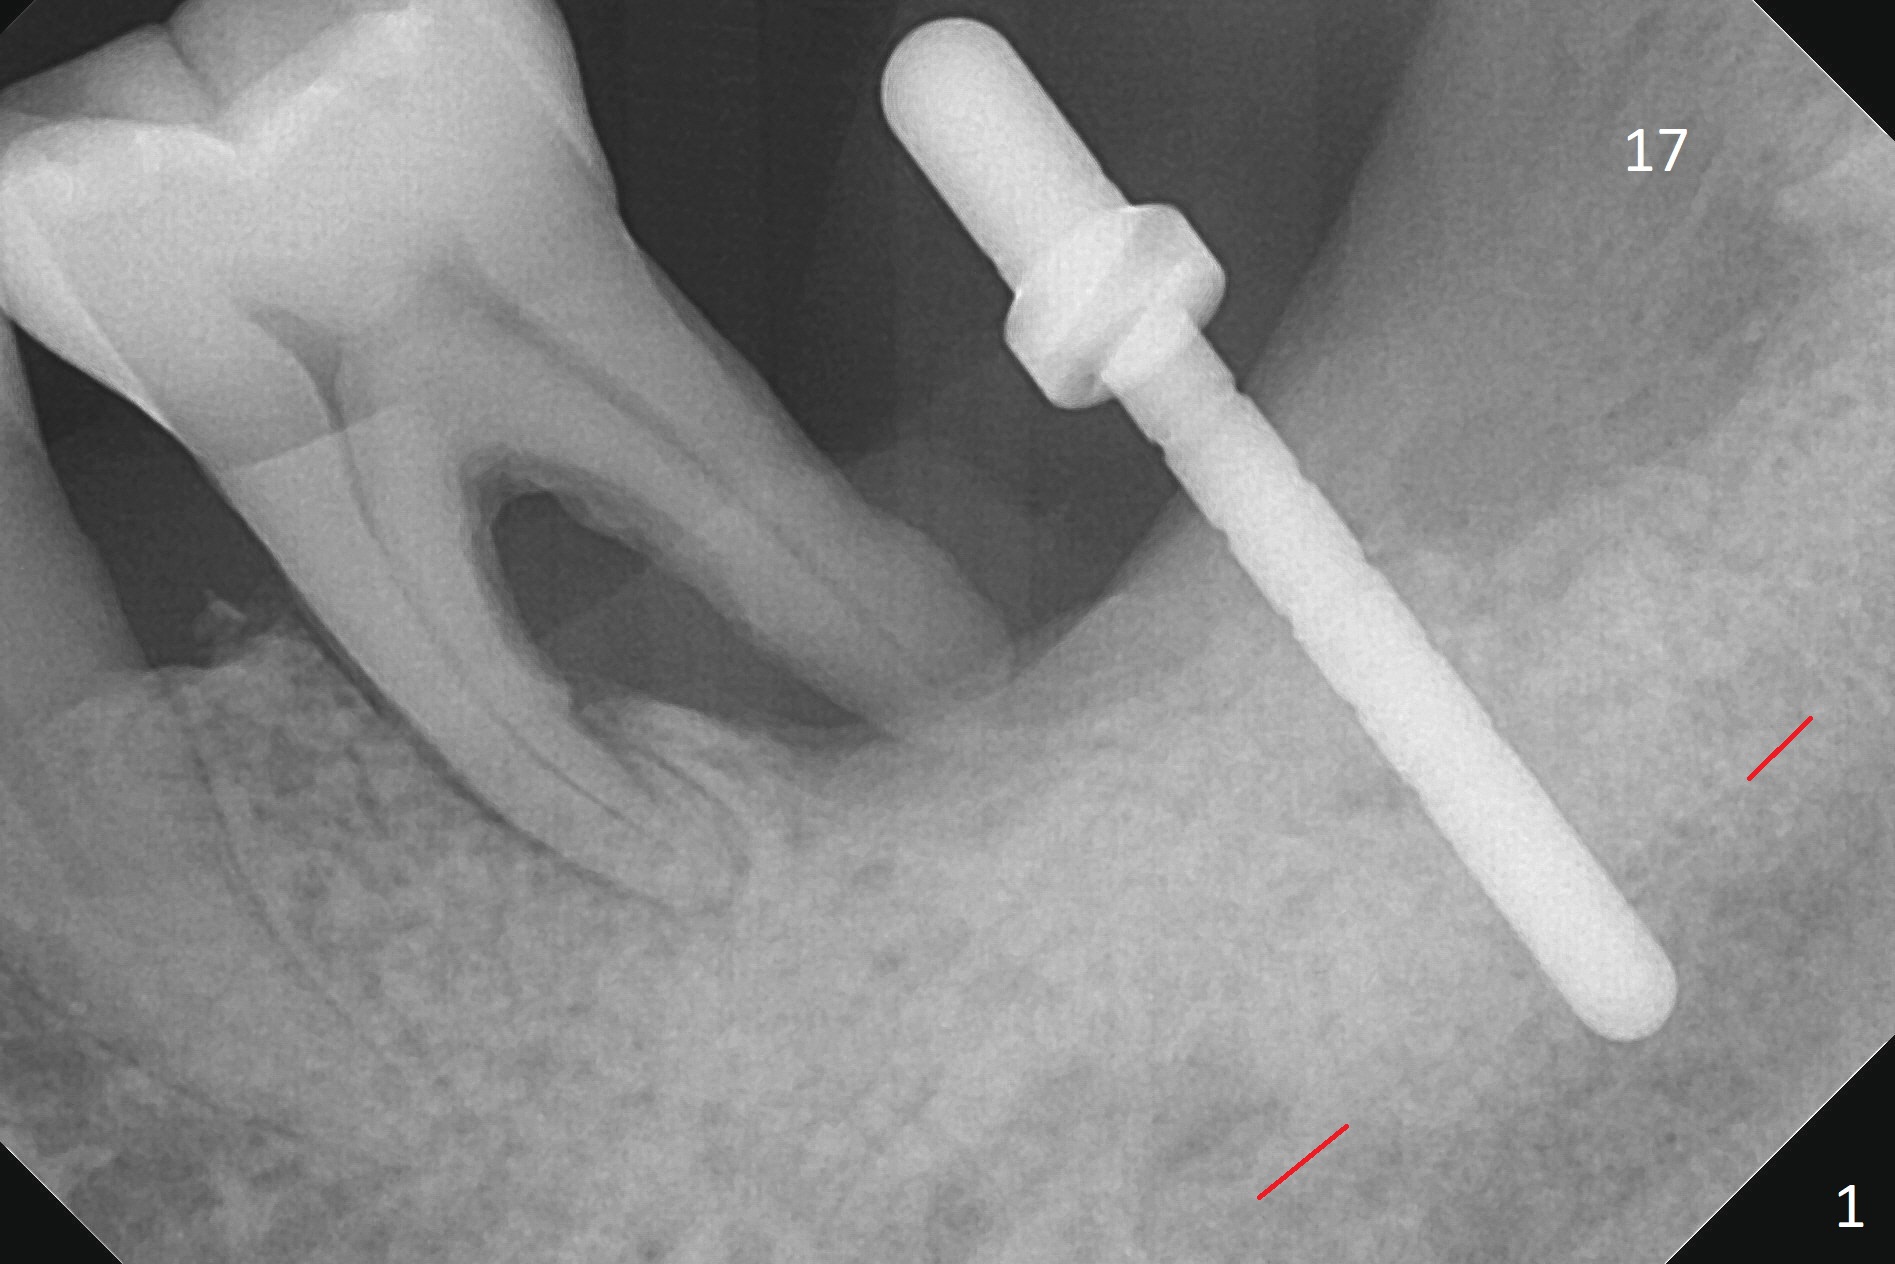

After extraction of the mesioangular tooth #17, initial osteotomy at #18 is 11 mm in depth with sudden empty feel (without pain with infiltration anesthesia); when a parallel pin is inserted, it goes down more than expected (Fig.1). Subsequent osteotomy is strictly controlled at the depth of 11 mm for 2.5 and 3.0 mm reamers. When 3.5 and 4.0 reamers are being used for ~ 9 mm, pain is confined to the coronal portion of the osteotomy, apparently associated with infection from the socket of #17 or from the distal apex of the tooth #19 (scaling & root planing done earlier). After addition of local anesthetic (infiltration), a 5x11 mm tap is inserted (Fig.2). With sufficient clearance from the Inferior Alveolar Canal (Fig.1-3 red dashed line), block anesthesia is administered. A 5x11 mm Tatum implant is placed with >50 Ncm (Fig.3). A 4.5x5 mm abutment is placed to increase retention of periodontal dressing. Impression is taken 4 months postop (Fig.4). The tooth #19 is symptomatic 7 months post #18 cementation.